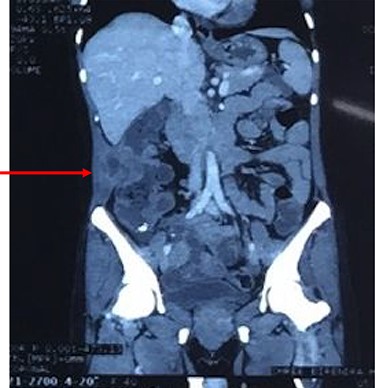

Computed tomography of the abdomen showing perforation of the tumor through muscles of lateral abdominal wall with abscess formation as seen on CT scan.

After resuscitation with intravenous fluids, administration of broad-spectrum intravenous antibiotics and intravenous analgesics, a contrast-enhanced computed tomography (CECT) scan was done to further characterize the lesion. CECT of abdomen showed large abscess extending from the subcutaneous and intermuscular planes over the right iliac fossa and breaching the peritoneum. It showed heterogeneous wall thickening of the proximal part of the ascending colon with loss of mural stratification and causing luminal narrowing, measuring 4.8 × 5.1 × 4.5 cm with surrounding inflammatory changes with adjacent well-defined collection 11.3 × 4.5 × 10.9 cm and few air pockets and infiltrating the right lower abdominal wall (Fig. 2). Pus aspirated from the right abdominal swelling and was sent for culture and sensitivity. Patient was taken up for diagnostic laparoscopy and proceeded.

Coronal reconstruction of CT shows mass extending from colon and invading into anterior abdominal wall. Arrows indicate the point of exit of mass through the abdominal wall musculature.